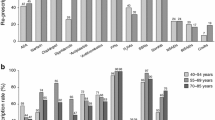

Results: Rebleed rates at 30 days were 7.7% and 13.6%, respectively, for the high-dose IV esomeprazole and no-IV esomeprazole treatment groups (equating to a number needed to treat of 17 in order to prevent one additional patient from rebleeding). In the US setting, the average cost per patient for the high-dose IV esomeprazole strategy was $US14 290 compared with $US14 239 for the no-IV esomeprazole strategy (year 2007 values). For the European setting, Sweden and Spain were used as examples. In the Swedish setting the corresponding respective figures were Swedish kronor (SEK)67 862 ($US9220 at average 2006 interbank exchange rates) and SEK67 807 ($US9212) [year 2006 values]. Incremental cost-effectiveness ratios were $US866 and SEK938 ($US127), respectively, per averted rebleed when using IV esomeprazole. For the Spanish setting, the high-dose IV esomeprazole strategy was dominant (more effective and less costly than the no-IV esomeprazole strategy) [year 2008 values]. All results appeared robust to univariate/threshold sensitivity analysis, with high-dose IV esomeprazole becoming dominant with small variations in assumptions in the US and Swedish settings, while remaining a dominant approach in the Spanish scenario across a broad range of values. Sensitivity variables with prespecified ranges included lengths of stay and per diem assumptions, rebleeding rates and, in some cases, professional fees.